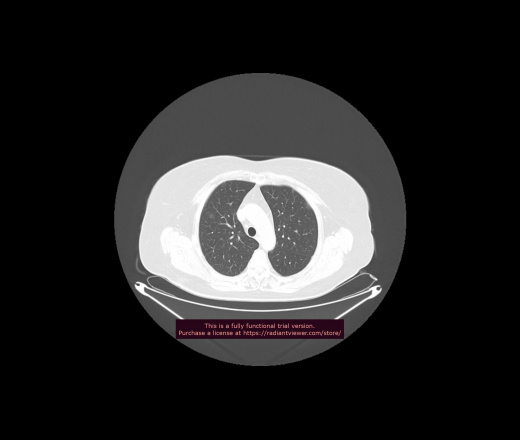

Уважаемые коллеги, если имеется интерес, сможете ли Вы спрогнозировать дальнейшее +-одинаковое течение процесса у 4 данных разных пациентов? Зацепиться где-то можно очень просто, где-то нельзя.